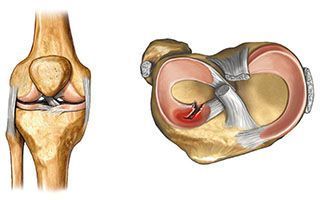

Пластика крестообразной связки — инвазивное вмешательство, целью которого является восстановление крестообразной связки. Оно предусматривает артроскопическую операцию на суставе, которая заключается в удалении повреждённой связки и её замене трансплантатом. Пластику крестообразной связки коленного сустава ещё называют реконструкцией или трансплантацией.

Операция на ПКС: виды пластики, принцип выполнения

Все виды пластики в современной медицине выполняются при помощи артроскопии с минимальным травматизмом.

Аутотрансплантация

Выполняется пересадка части сухожилий пациента, которые хирург берет из области связок и сухожилий надколенника. Срезается тонкий слой, что не вызывает дальнейшего дискомфорта у человека. При выборе данного метода извлекаются травмированные ткани, и проводится замещение здоровыми связками. Края срезанных сухожилий крепятся в отверстиях большой берцовой и бедренной кости, после чего натягиваются и фиксируются биоразлагаемыми материалами. Спустя несколько месяцев все материалы приживаются к костной ткани. Из-за огромной практической базы и высокого процента успешного приживления специалисты в первую очередь отдают предпочтение аутотрансплантации.

Аллотрансплантация

При выборе этого метода связки для пересадки срезаются не у пациента, а у донора. При помощи этого метода не выполняется пластика нецелостной передней крестообразной связки коленного сустава. Так как используется чужеродный трансплантат, шанс отторжения очень высокий. Отличий в плане фиксации и последовательности действий по сравнению с аутотрансплантацей нет. Назначается аллотрансплантация в редких случаях, если невозможно выполнить забор трансплантата у пациента.

Операция по пластике задней и передней крестообразной связки в клинике ЦЭЛТ выполняется эндоскопически и является малотравматичной. Она проводится через небольшие проколы, в которые вводят артроскоп и инструменты. Такой способ позволяет провести диагностику коленного сустава изнутри и выявить все его повреждения.

Все данные выводятся на монитор. Наш специалист удаляет остатки крестообразной связки, осуществляет забор сухожилий из полусухожильной и тонкой мышцы бедра и формирует из них трансплантат связки, который и заменяет собой повреждённую связку. Хирург натягивает и фиксирует его в костном канале при помощи фиксаторов. Всё это позволяет трансплантанту по мере заживления и восстановления трансформироваться в полноценную связку.